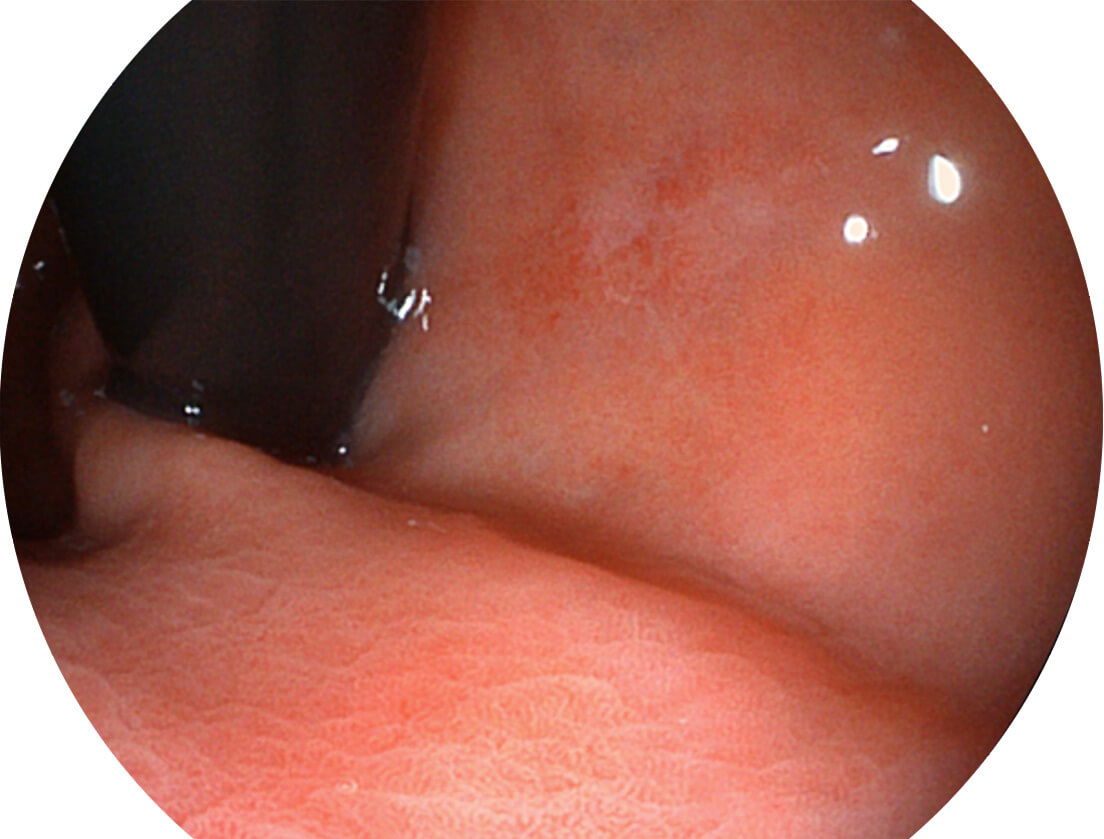

图像具有高亮度、高黏膜血管颜色对比度的特点,且不改变粘液、食物残渣、粪便的基本颜色,可在中远景下进行观察,助力消化道早期疾病的诊断。

• 白光图像 SFI图像